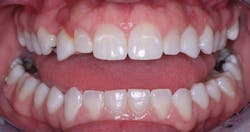

If teeth are impaired esthetically, and the patient has a sincere desire to look more acceptable, the alternatives are bleaching (whitening), crowns, or veneers. If the teeth are acceptable functionally and only defective from an esthetic standpoint, bleaching or veneers are indicated. Bleaching is by far the best and least aggressive choice if that procedure is feasible.

If the lingual or occlusal surfaces are intact, the teeth are anterior teeth, the occlusion is not abusive, and caries is not a major problem, then veneers are the best solution. They can also be the best solution on some premolar teeth that are not in heavy occlusion.

If the teeth are either functionally unacceptable and/or both functionally and esthetically unacceptable, crowns are indicated.

All of the above situations and many more necessitate tooth reshaping and rebuilding to establish adequate occlusal function and esthetics. Crowns are the obvious solution, assuming the patient has the financial resources to have the treatment accomplished (figures 1-3).